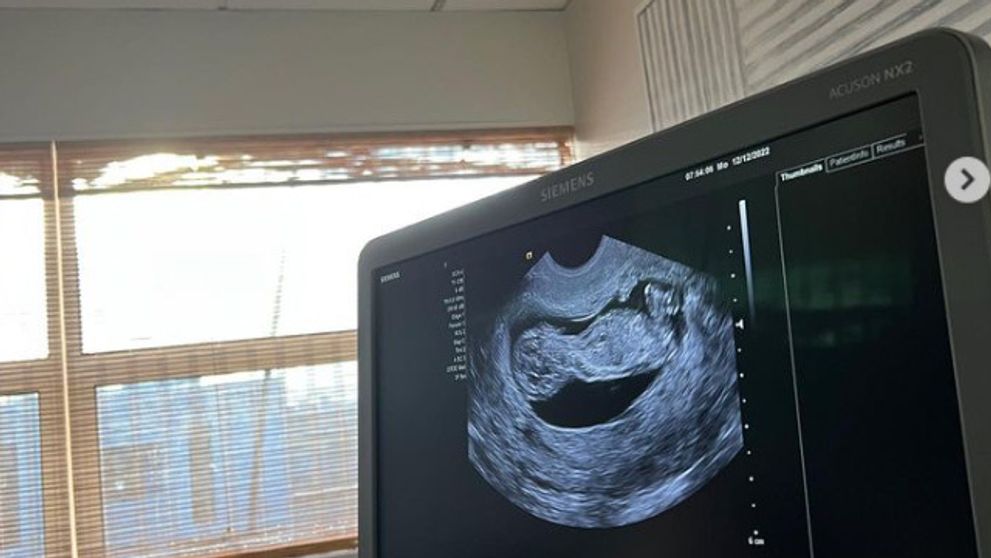

„Posledných pár rokov bolo prinajmenšom zaujímavých, ale zistila som, že práve tie najnáročnejšie obdobia v živote môžu byť najzábavnejšie. Týchto niekoľko mesiacov mimo športu mi skutočne prinieslo novú lásku a uznanie pre hru, ktorej som zasvätila život,” napísala k snímke z ultrazvuku slávna tenistka.